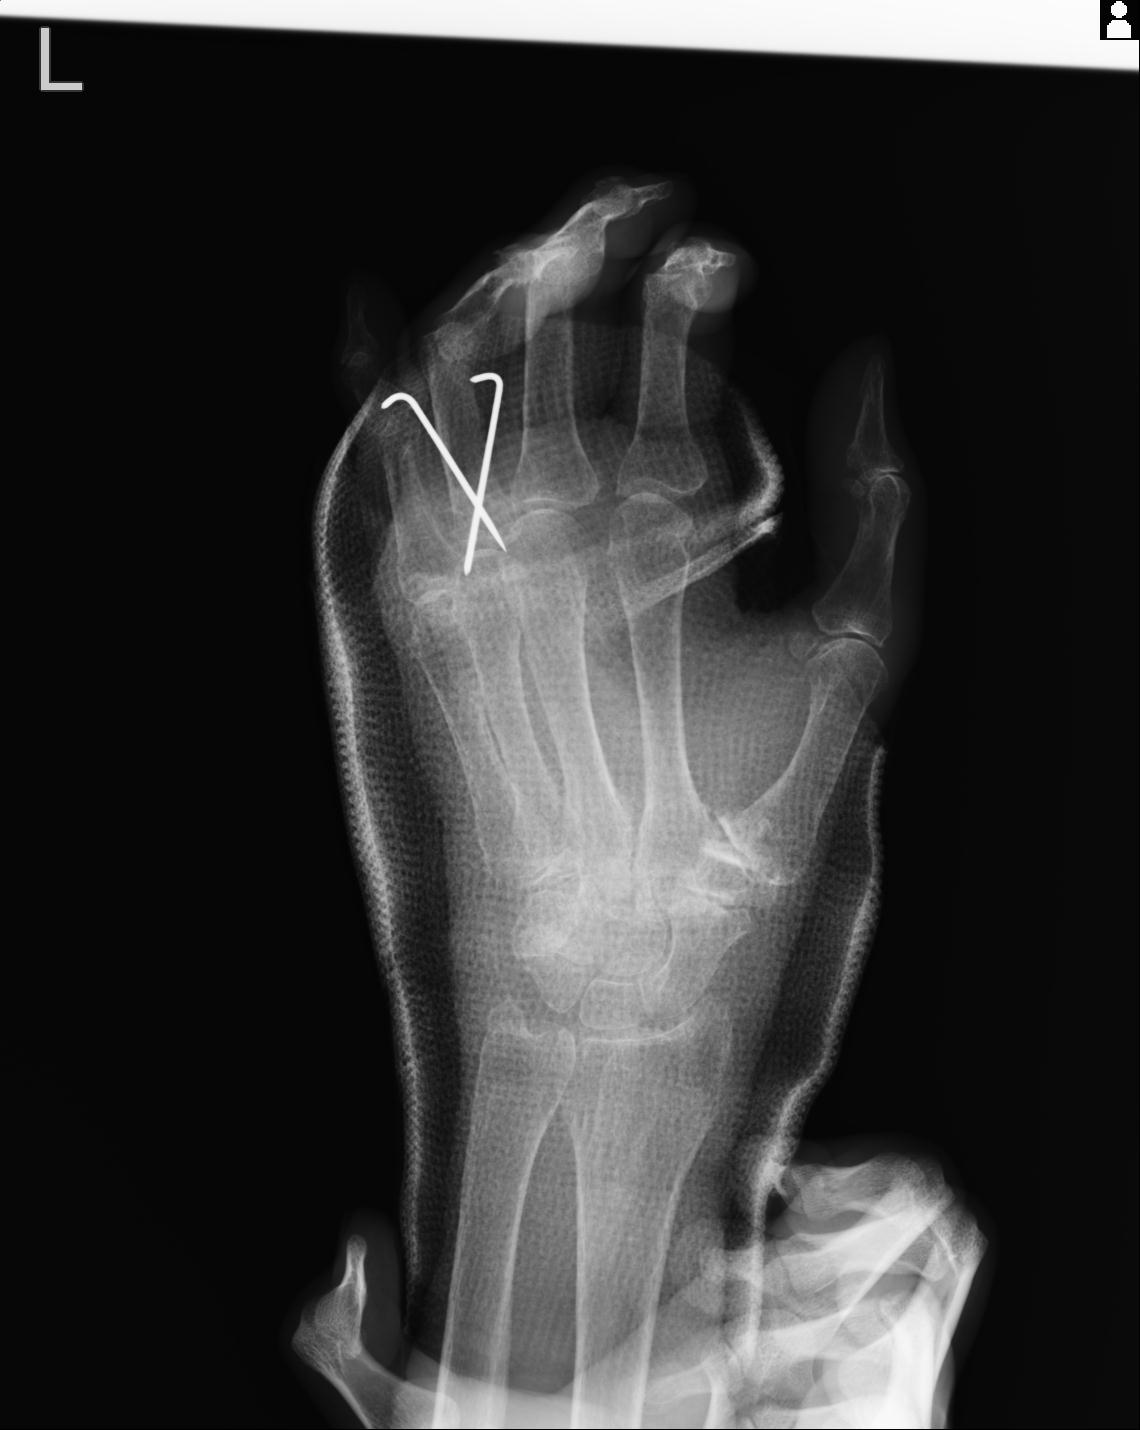

102766 1/5 1/12 左手関節 4R 28歳男性 左橈骨遠位端